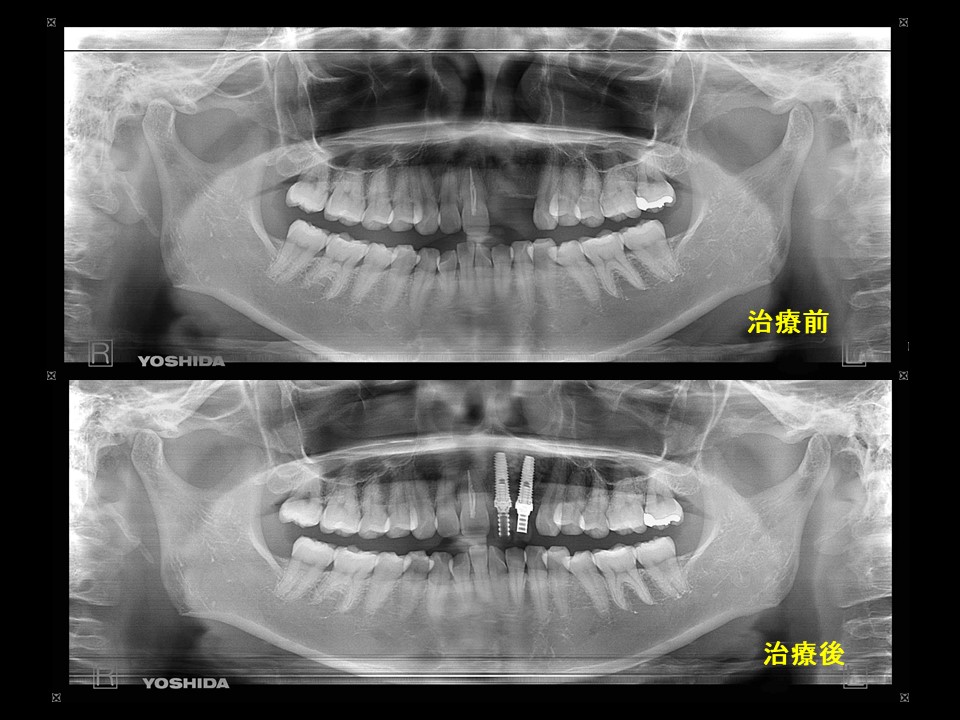

症例19